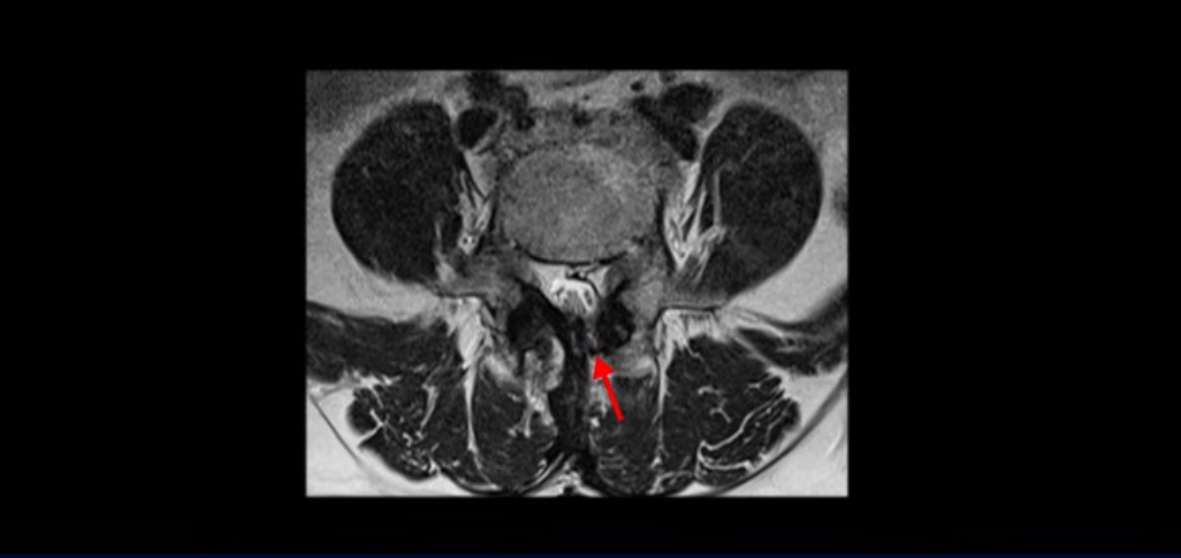

이분은 허리 다섯 마디 중 4번 5번, 5번 1번에 감압술로 눌린 신경을 풀어주는 수술을 받았습니다.

후관절을 떼어낸 흔적이 보입니다.

단면으로 보면 왼쪽 후궁을 제거한 흔적이 보입니다.

5번 1번도 왼쪽 후궁을 열고 수술 받았습니다.

하지만 중심성 협착은 여전히 심한 상태입니다.

이분은 오른쪽, 왼쪽 다리에 모두 방사통이 심하고 왼쪽 다리에 마비 증상, 즉 풋드랍(족하수) 증상이 있습니다. 왼쪽 신경 가지가 빠져나가는 추간공을 보면 두 마디가 좁아져 있습니다.

이런 신경 구멍이 좁아져 있는 걸 협착이라고 합니다.

이미 앞선 두 번의 수술로 뼈와 인대 등을 일부 제거해서 안정성이 떨어진 상태에서 추가로 수술하려니까 척추가 너무 불안정해져 무너질 게 걱정되니까 이번에는 나사 박는 유합술을 권유 받은 겁니다. 이런 환자분들의 방사통과 마비 증상이 어떻게 수술 없이 좋아질 수 있을까요? 치료는 어떻게 하는 걸까요?